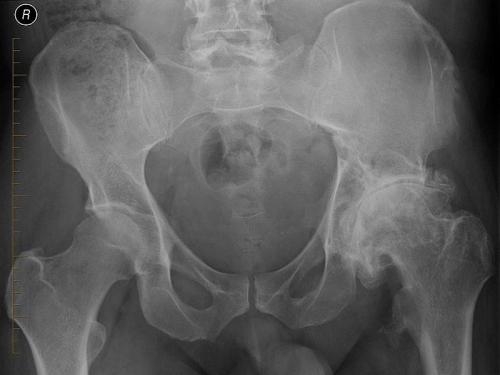

Деформирующий остеоартроз левого ТБС. Обратите внимание, как изменились очертания левого суставного сочленения по сравнению с правым.

Остеоартроз тазобедренного сустава 2 степени характеризуется выраженным уменьшением пространства в суставной щели. В таком состоянии хрящи уже сильно повреждены, что провоцирует постоянное трение костей при движении и выраженную боль у пациента. Из-за развития отечности сустав теряет свои функции.

Выявить 2-ю степень несложно, так как при первом же рентгеновском снимке врач заметит существенные отклонения. Характерные признаки второй степени заболевания:

Признаки остеоартроза сустава 3 степени :

- сильный хруст в суставе , который развивается во время движения (от трения костей);

- постоянные сильные боли, которые очень сложно купировать обычными анальгетиками;

- болезненная пальпация;

- значительная деформация;

- активный воспалительный процесс;

- потеря возможности передвигаться без трости или костылей.